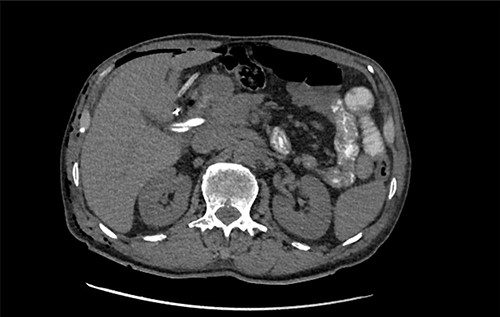

Subsequent review of preoperative imaging solved the mystery. Duplicated gallbladder with double cystic ducts was clearly evident on CT and magnetic resonance imaging (MRI) which were hidden in plain sight (Figs 4–7). CT cholangiogram (Fig. 3) was performed Day 1 post-operatively showing the double cystic duct with no evidence of bile leak. Rest of patient’s admission was uneventful and he was cleared for discharge on Day 5 post-operatively. Patient remains well and was back to his daily activities during his follow-up review.

Axial section of preoperative CT abdomen from initial presentation showing thickened gallbladder with pericholecystic fluid; duplicated gallbladder evident, initially thought to be Phrygian cap sign.